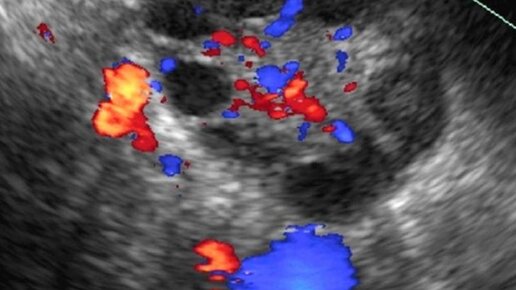

Серозная / муцинозная / папиллярная ЦИСТАДЕНОМА яичника

Цистаденома яичника на УЗИ что это такое

Заболевание, которое называют цистаденомой яичника, — доброкачественное новообразование (опухоль) у женщин или девушек молодого и среднего возрастов. Строение такой опухоли приближено к кистозному и в соотношении к твёрдой ткани, жидкость составляет около 25%. За стандартный размер опухоли принято считать новообразование от 3 до 15 сантиметров, толщина 1-2 миллиметра. Существует ряд образований, который легко перерождается в злокачественную форму. Причины заболевания Источник возникновения заболевания так и не был найден до сегодняшнего дня...